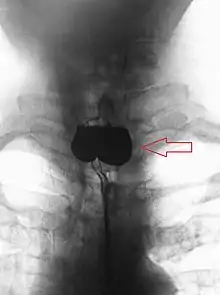

A combination of the simple barium swallow and a thorough endoscopy will normally confirm the diverticulum.[4]